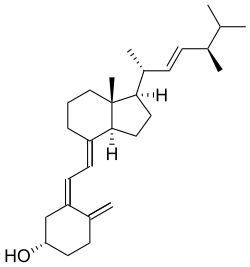

Sufficient vitamin D levels can also be achieved through dietary supplementation and/or exposure to sunlight. Vitamin D3 (cholecalciferol) is the preferred form since it is more readily absorbed than vitamin D2. Most dermatologists recommend vitamin D supplementation as an alternative to unprotected ultraviolet exposure due to the increased risk of skin cancer associated with sun exposure. Endogenous production with full-body exposure to sunlight is approximately 250 μg (10,000 IU) per day.[59]